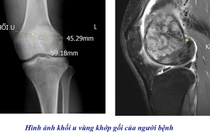

BSCKII Nguyễn Thế Huy, Phó khoa Nội tim mạch người lớn cho biết về tình trạng nguy kịch của người bệnh, thông qua kết quả siêu âm tim và chụp MSCT của người bệnh cho thấy, van động mạch chủ của bệnh nhân rất vôi hóa, tổn thương hẹp nặng.

Diện tích lỗ van, vốn trung bình ở người bình thường là 3-4 cm2, nay của bệnh nhân chỉ còn khoảng 0,5 – 0,8 cm2, cho thấy mức độ hẹp khít nguy hiểm, kèm theo các triệu chứng điển hình của bệnh hẹp van động mạch chủ nặng, báo hiệu tiên lượng xấu nếu không can thiệp kịp thời.